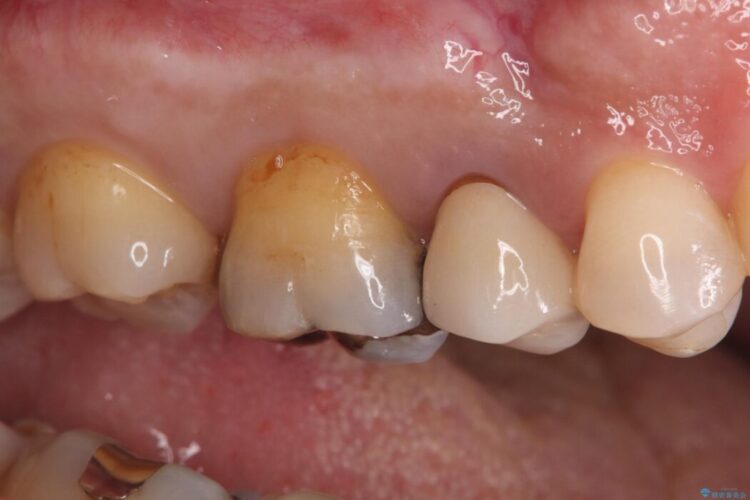

検査の結果、銀歯の下の歯質が薄くなっており、このままだと割れてしまう(破折)リスクが高い状態でした。

歯を長く守るため、セラミッククラウンでしっかりと補強し、強度と自然な見た目を両立させる治療をご提案しました。

まず、古い銀歯を丁寧に外し、内部に虫歯がないか確認しました。

その後、残りの歯を保護して強度を上げるため、適合性が高いオールセラミッククラウンの作成・装着を行いました。